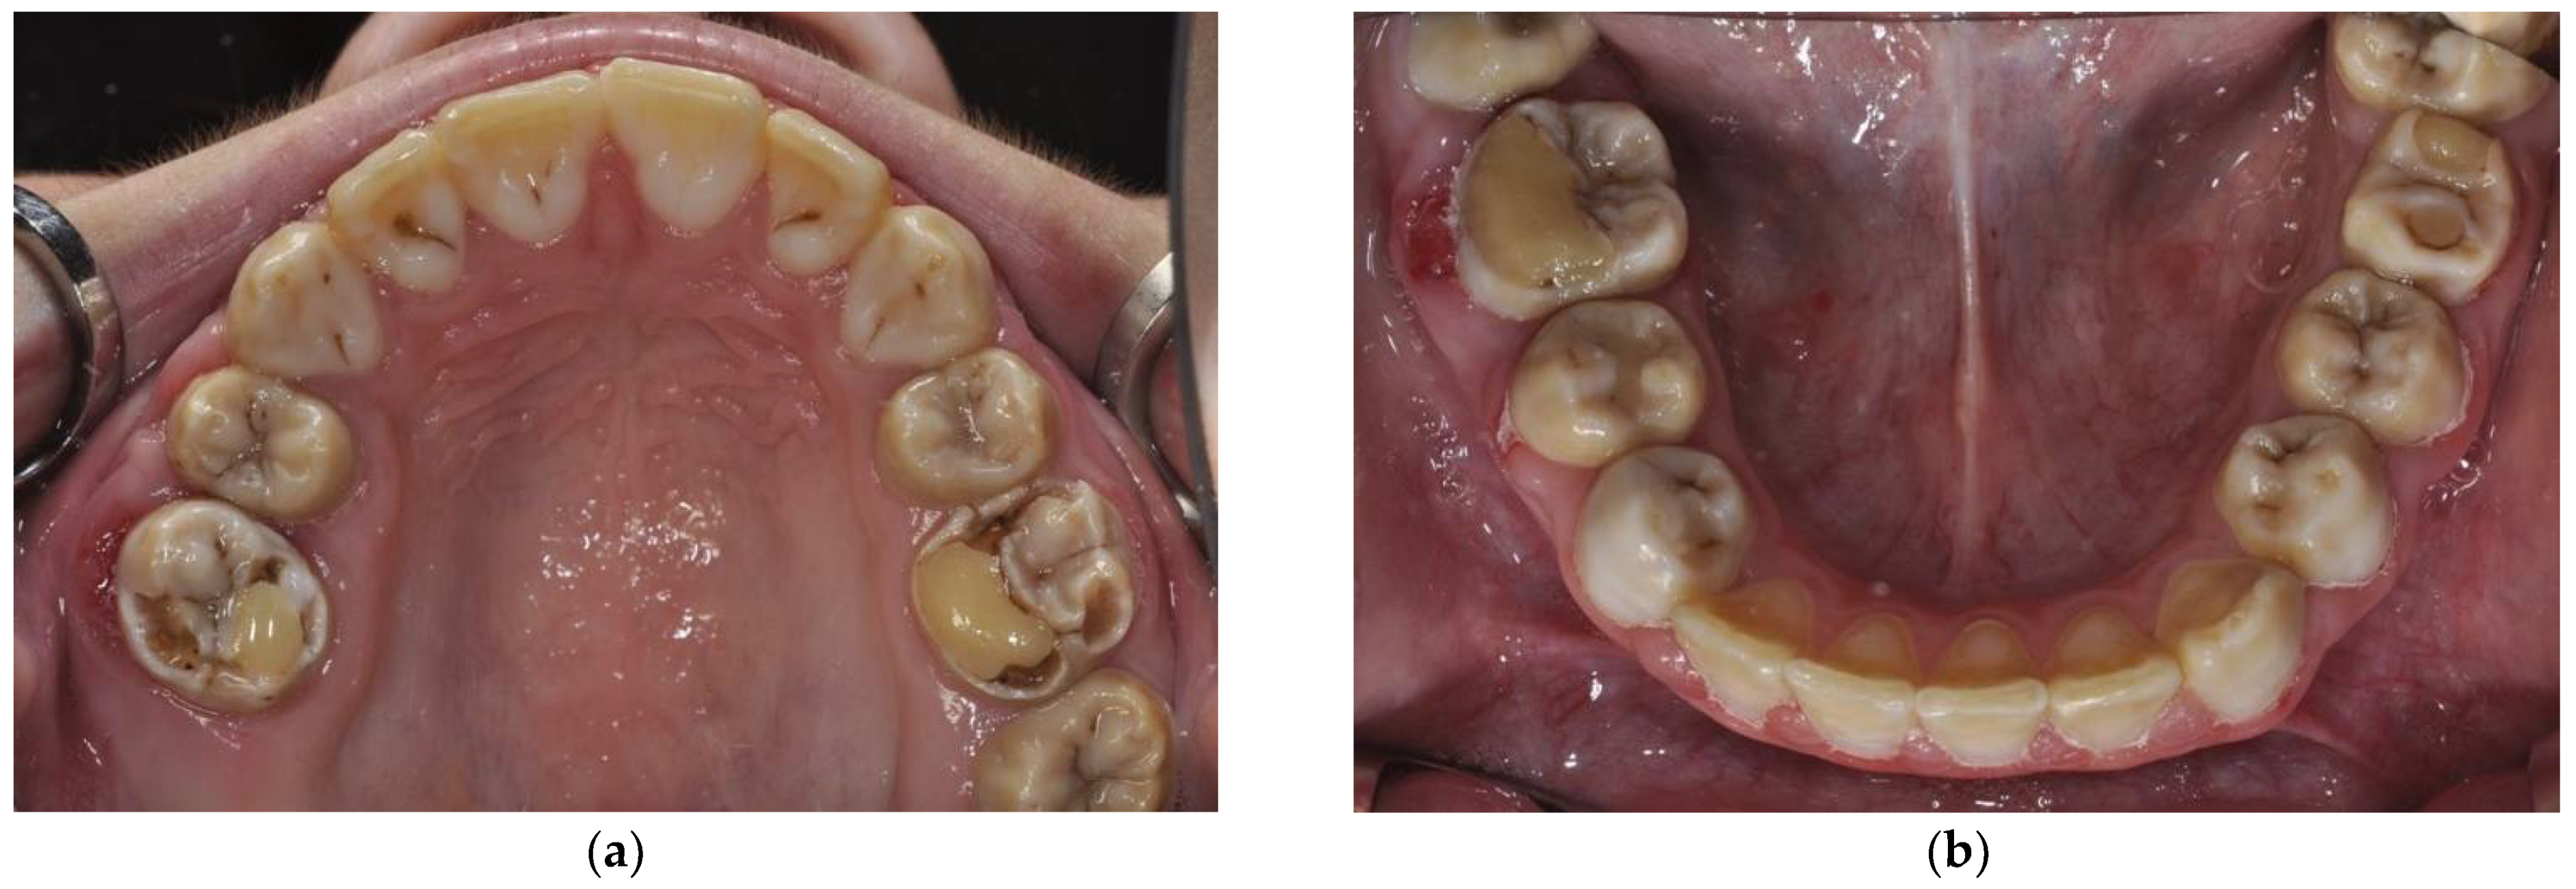

2.1. Case Report 1: Mixed Dentition